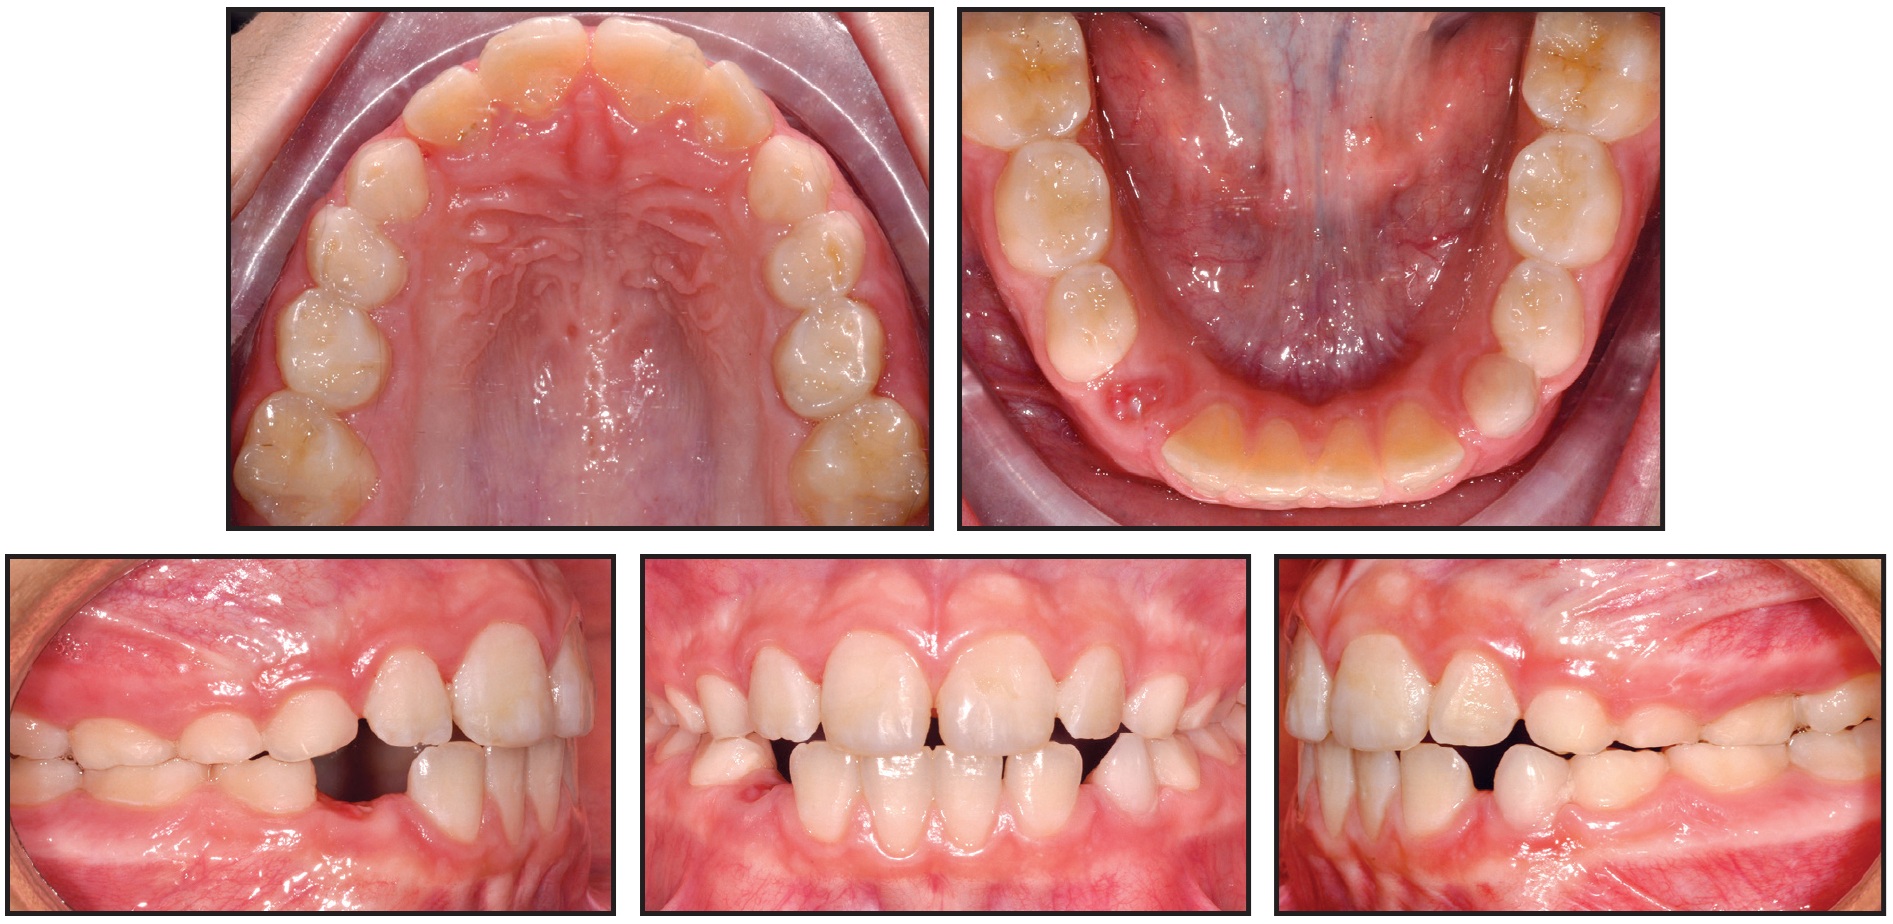

A 7-year-old female in the mixed dentition presented with a crossbite associated with a right lateral deviation of the mandible and a transverse deficiency (Fig. 8).

Fig. 8 Case 2. A. 7-year-old female patient with maxillary transverse deficiency, crossbite, and mandibular deviation before treatment. B. Arch-width measurements (mm) on STL digital casts obtained from intraoral scan.